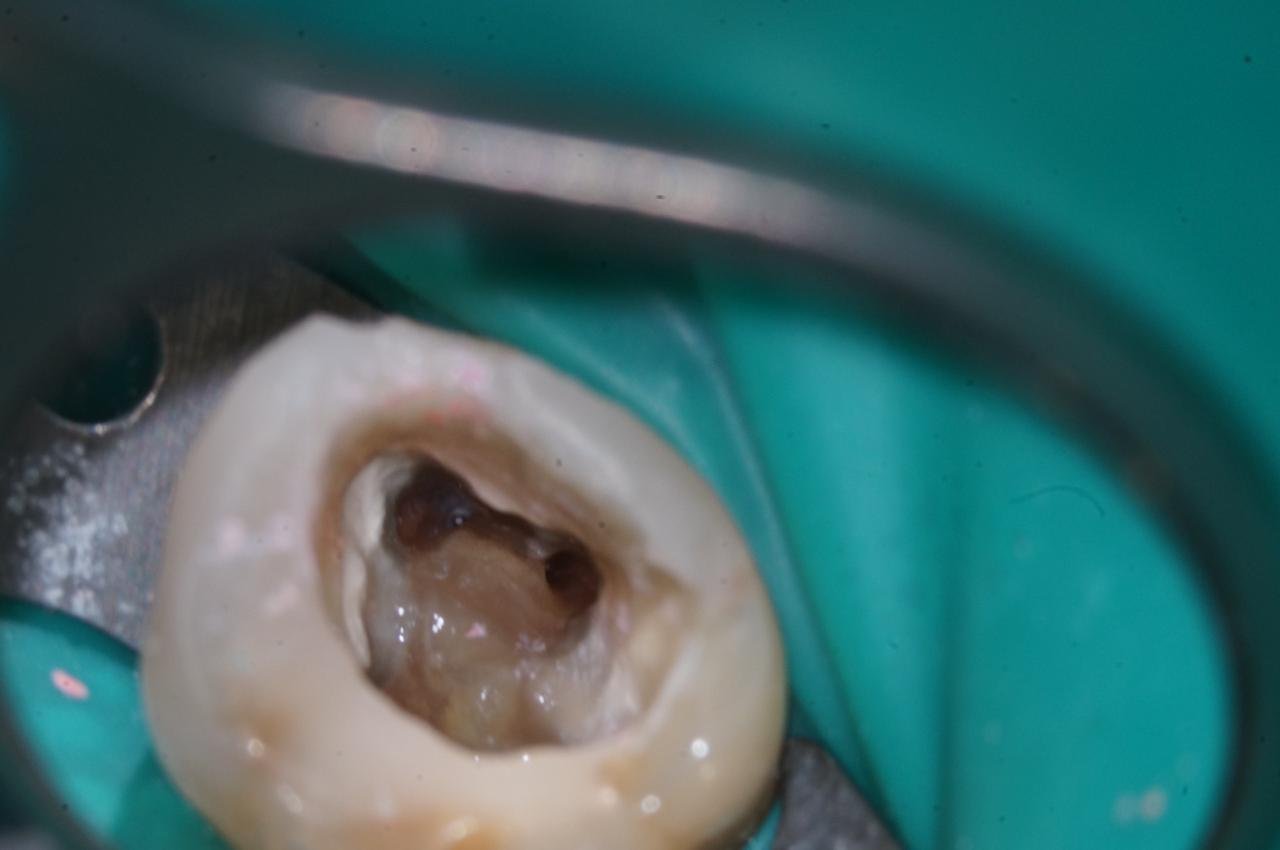

Смотрите, вот зуб на платке, изолирующем его от слюны (к другой стороне зуба всё ещё прикреплён пациент):

А вот так его видно в микроскоп:

Видите? Канал чистый.